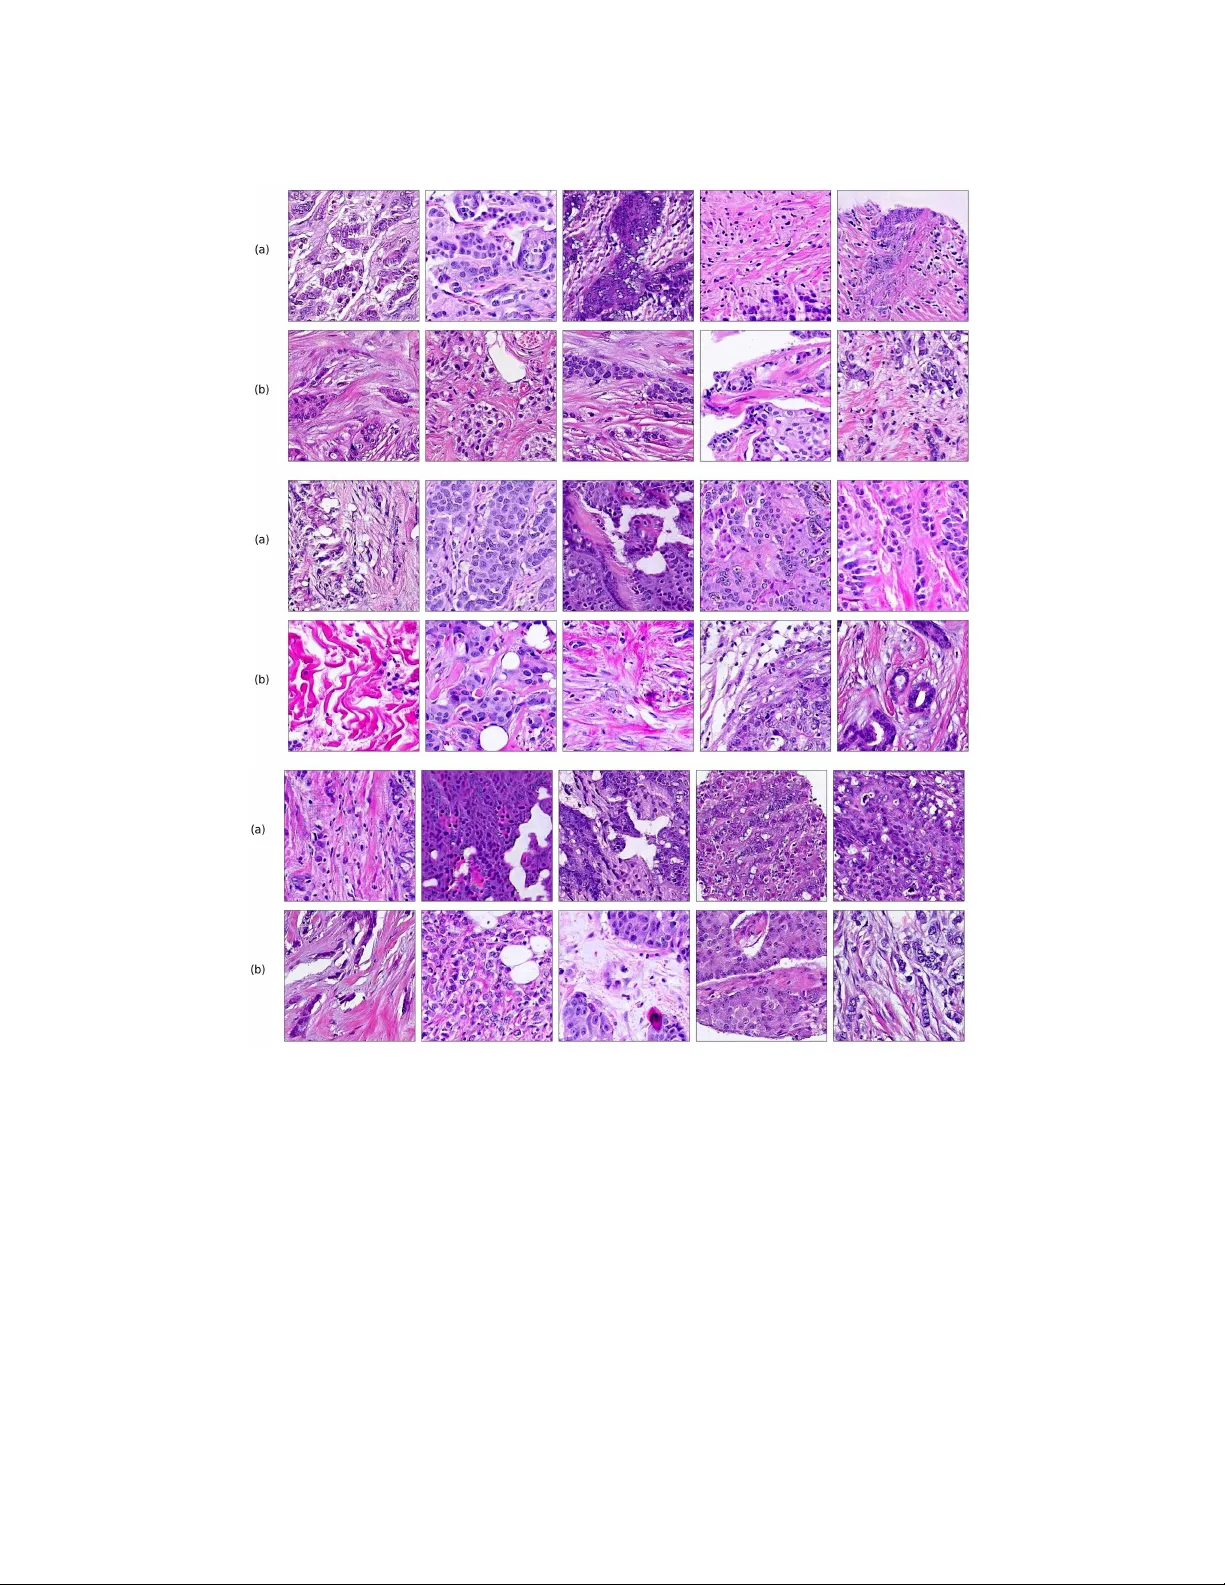

** 본 논문은 병리학 이미지에서 조직 형태와 세포 구성을 자동으로 학습하고, 이를 기반으로 고품질 합성 이미지를 생성하는 새로운 GAN 프레임워크인 PathologyGAN을 제안한다. 기존의 지도 학습 기반 병리학 연구는 라벨링 비용이 높고, 라벨이 조직의 미세 환경을 완전히 포착하기 어렵다는 한계가 있다. 이를 극복하고자 저자들은 비지도 학습, 특히 표현 학습 능력을 갖춘 생성 모델을 활용한다. **모델 설계** PathologyGAN은 BigGAN을 기본 구조로 채택하고, StyleGAN‑2의 매핑 네트워크와 스타일 믹싱, AdaIN을 도입해 잠재 공간을 보다 해석 가능하고 조작 가능하게 만든다. 매핑 네트워크는 4‑layer ResNet으로 구성돼, 표준 정규분포에서 샘플링된 잡음 z 를 고차원 잠재 벡터 w 로 변환한다. 이 과정은 잠재 차원에서의 비선형 변형을 촉진해, 조직의 색상·텍스처·세포 밀도와 같은 고수준 특성을 별도의 차원에 분리한다. 스타일 믹싱은 두 개의 서로 다른 z 를 동일한 생성기에 투입하고, 중간 레이어에서 교체함으로써 “고수준 특성”이 특정 레이어에 국한되도록 강제한다. 이는 잠재 공간에서 의미론적 벡터 연산이 실제 이미지 변형으로 직결되게 만든다. 판별기에는 Relativistic Average Discriminator(RAD)를 적용했다. RAD는 단순히 “진짜인지 가짜인지”를 판단하는 것이 아니라, 실제 샘플이 가짜보다 더 현실적인 확률을 추정한다. 이를 통해 학습이 더 안정화되고, 기존 hinge loss 대비 빠른 수렴과 높은 이미지 품질을 얻을 수 있었다. **데이터 및 전처리** 두 종류의 데이터셋을 사용했다. (1) 독일 NCT에서 제공한 대장암 슬라이드 86장, 총 100 K 패치(224 × 224)와 10가지 조직 라벨(지방, 배경, 파편, 림프구, 근육 등). (2) 네덜란드 NKI와 캐나다 VGH에서 수집한 유방암 TMA 576개, 환자 576명, 총 249 K 학습 패치와 62 K 테스트 패치. 패치 추출 시 50 % 겹치게 슬라이딩하고, 회전·수평·수직 반전 등 기본 증강을 적용했으며, 조직이 70 % 이상 차지하는 패치만 사용했다. 학습은 NVIDIA Titan RTX 24 GB GPU에서 72시간 동안 진행됐으며, Adam 옵티마이저(β₁=0.5, lr=1e‑4)를 사용하고 판별기 5 step : 생성기 1 step 비율을 유지했다. **성능 평가** ① **이미지 품질**: Fréchet Inception Distance(FID)를 사용해 10 K 생성 이미지와 10 K 실제 이미지를 비교했다. 유방암에서 16.65, 대장암에서 32.05라는 점수를 얻어, 기존 디지털 병리학 GAN 대비 우수한 품질을 입증했다. ② **조직학적 의미**: CellProfiler를 이용해 각 패치에서 암세포, 림프구, 기질세포 수·밀도를 정량화하고, 이를 Inception‑V1 특징에 결합해 FID를 재계산했다. 결과는 9.86으로, 생성 이미지가 실제 조직의 세포 구성을 정량적으로도 잘 재현함을 보여준다. ③ **잠재 공간 해석**: “암세포 밀도 증가” 벡터, “림프구 비율 증가” 벡터 등을 잠재 벡터에 선형적으로 더했을 때, 생성 이미지에서 해당 조직 특성이 눈에 띄게 변한다. 이는 잠재 공간이 의미론적으로 정렬되어 있음을 의미한다. ④ **전문가 평가**: 두 명의 병리학자가 블라인드 방식으로 200여 장의 실제·생성 이미지를 평가했으며, 통계적으로 유의미한 차이를 보이지 않았다. 이는 PathologyGAN이 임상 수준의 시각적 신뢰성을 확보했음을 의미한다. **추가 실험** Appendix B에서는 5 K, 10 K, 20 K 규모의 소규모 데이터셋에서도 모델이 수렴하고 의미 있는 잠재 표현을 학습함을 확인했다. Appendix C에서는 hinge loss 기반 모델이 조직 구조를 제대로 재현하지 못함을 시각적으로 제시했다. **공헌 및 향후 방향** 1. BigGAN에 StyleGAN‑2 요소와 RAD를 결합해 조직 이미지에 특화된 고품질 GAN을 구현. 2. FID와 세포 정량화 지표를 동시에 사용해 이미지 품질과 조직학적 의미를 정량화. 3. 의미론적 잠재 공간을 구축해 벡터 연산으로 조직 특성 변환이 가능하도록 함. 4. 코드·사전 학습 모델을 공개해 재현성을 보장하고, 다중 암종·다중 모달 데이터와의 통합 연구 기반을 제공. 향후 연구에서는 (i) 조직 라벨이 없는 대규모 WSI 전체에 대한 학습, (ii) 면역조직화학·공간 전사체와 같은 멀티모달 데이터와의 연계, (iii) 생성된 이미지 기반 데이터 증강을 통한 지도 학습 모델 성능 향상 등을 탐색할 수 있다. **